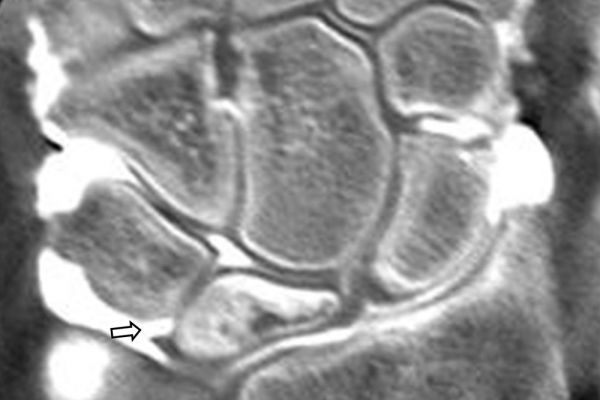

Είναι μια ελάχιστα επεμβατική απεικονιστική μέθοδος που επιτρέπει τη λεπτομερέστερη διερεύνηση του εσωτερικού των αρθρώσεων. Η ασφαλής έγχυση σκιαγραφικού εντός της άρθρωσης υπό ακτινολογική καθοδήγηση και η ακόλουθη απεικόνιση της άρθρωσης με αξονική ή μαγνητική τομογραφία (ή και με συνδυασμό των μεθόδων) αποσαφηνίζει βλάβες του χόνδρου και κακώσεις-ρήξεις συνδέσμων και τενόντων με υψηλή ακρίβεια, συμβάλλοντας σημαντικά στο λεπτομερή χειρουργικό σχεδιασμό.